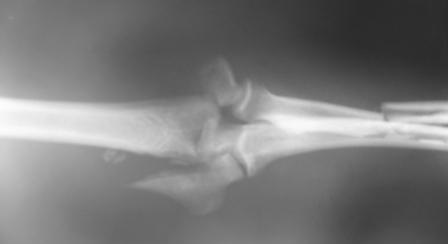

Больной Б. 43 лет, находится в клинике с диагнозом: Автотравма от

17.12.08 г. Открытый (3а) оскольчатый чрезмыщелковый перелом левой

плечевой кости, закрытые оскольчатые переломы диафизов костей левого

предплечья.